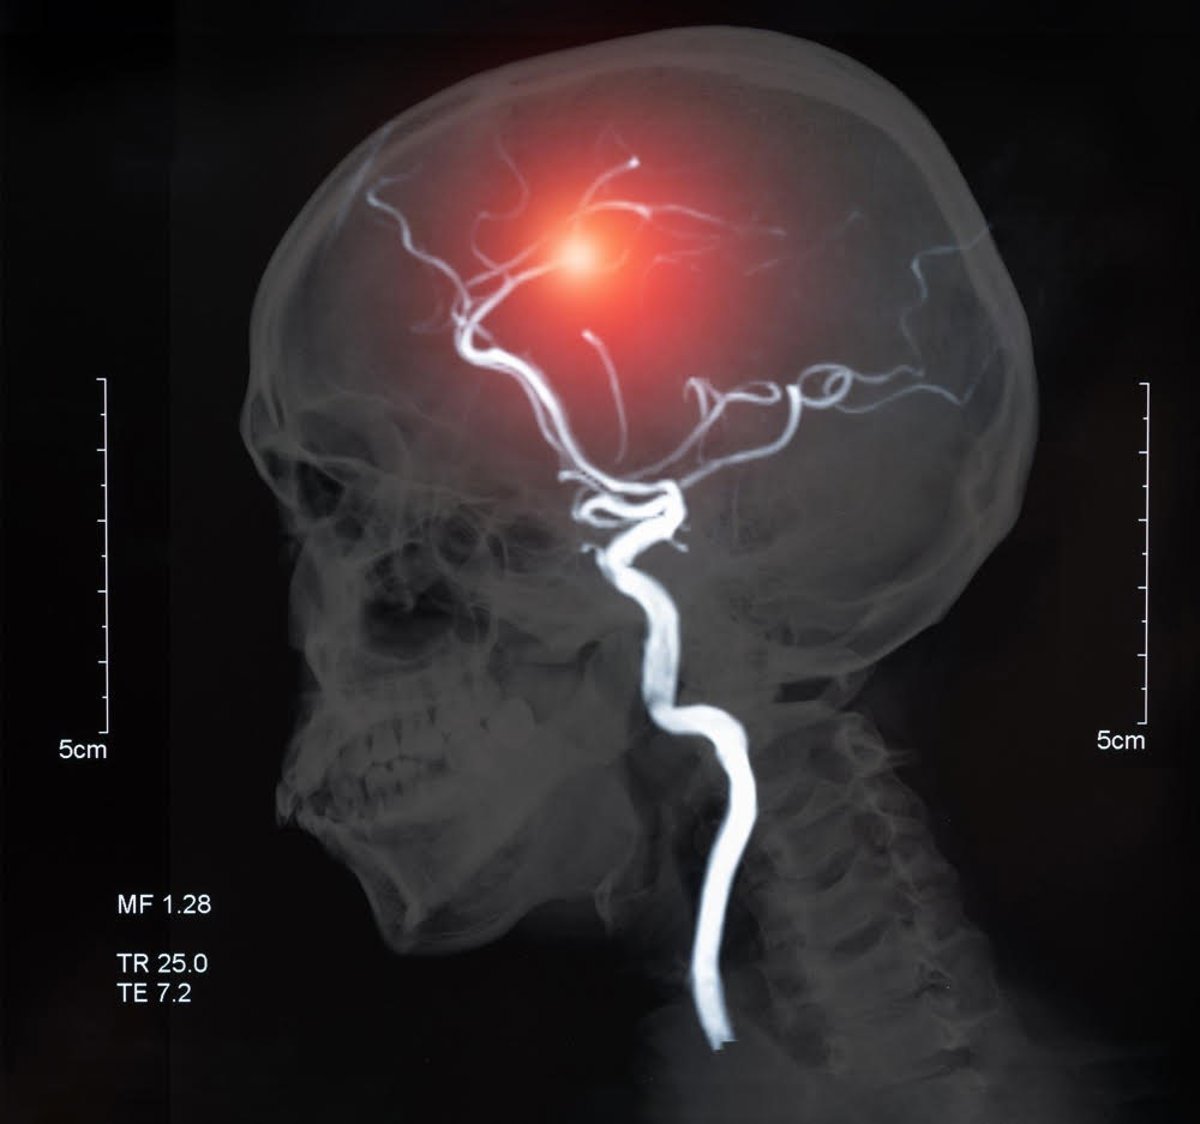

El ictus o accidente cerebrovascular es un trastorno brusco de la circulación cerebral que altera la función de una determinada región del cerebro. Ocurre cuando el flujo sanguíneo cerebral se interrumpe de manera brusca debido a la oclusión de una arteria cerebral por

un coágulo o una placa de ateroma (ictus isquémico) o bien por la rotura de una arteria cerebral, originando un ictus hemorrágico.